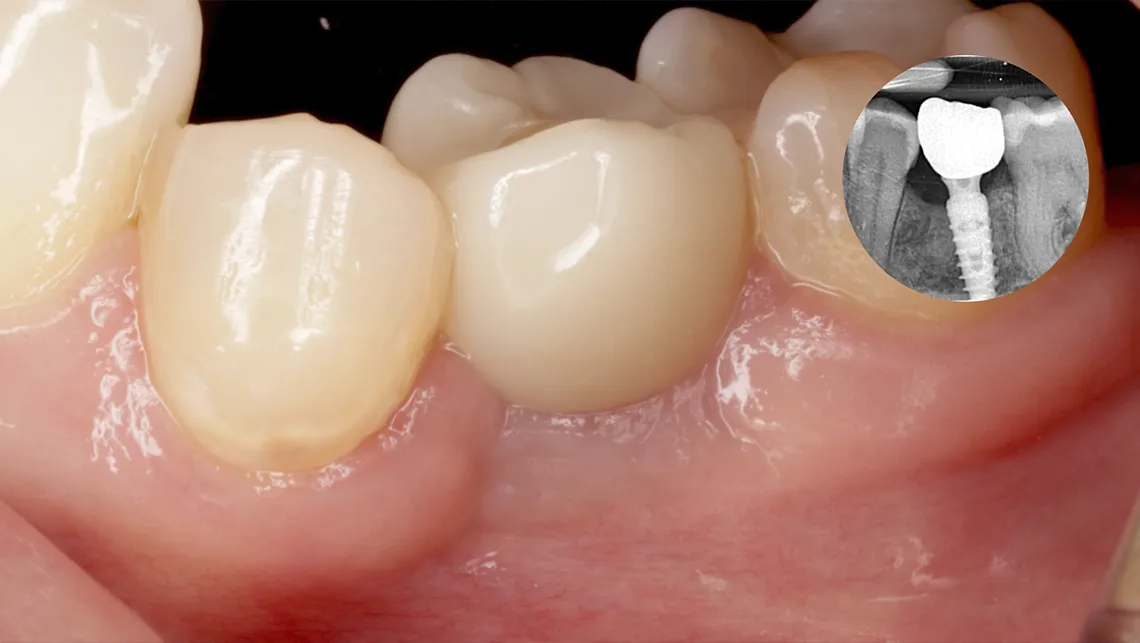

En el contexto actual de la implantología, donde se priorizan procedimientos mínimamente invasivos y los resultados predecibles, la oseodensificación se consolida como una herramienta clave para todos aquellos clínicos avanzados, con una base científica sólida y un potencial de aplicación en continuo crecimiento (figura 11, 12, 13, 14, 15, 16 y 17).

Fig. 13.  Fotografía del control de estabilidad biológica con sistema Osstell, tras la instalación de un implante postextracción Galimplant con oseodensificación

Fig. 14. Técnica SPOT.

Fig. 15. SPOT, implante instalado

Fig. 16. Implante cicatrizado a 9 semanas

Fig. 17. SPOT. Restauración final

Asimismo, la técnica SPOT (Selective Preservation of Tooth) representa una evolución del concepto de Socket Shield, al estandarizar la preparación del escudo radicular y la osteotomía mediante oseodensificación. Este enfoque permite preservar tejidos duros y blandos, mejorar la estabilidad primaria y optimizar la cicatrización temprana (figura 18).